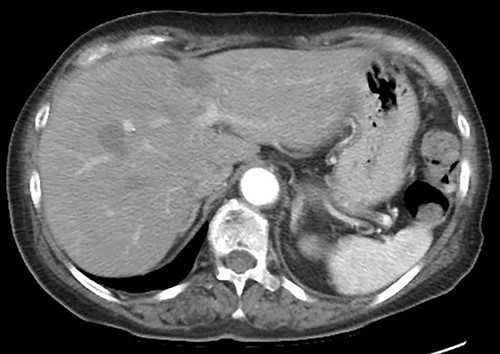

A 75-year-old bedridden woman presented to our hospital with chief complaints of epigastric pain, anorexia and a palpable mass in the epigastric region. She had a history of surgery for meningioma, but no history of abdominal surgery. Ultrasonography revealed a well-defined large cystic lesion with a long diameter of approximately 150 mm in the left liver lobe. Contrast-enhanced computed tomography showed a giant hepatic cyst with an irregular mass in liver segment 4, 20 × 16 cm in size (Fig. 1).